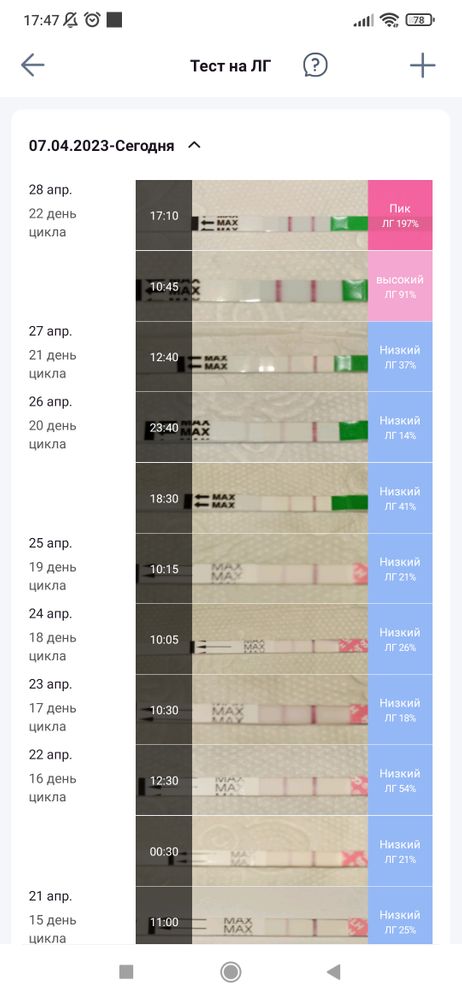

Тесты на О. 17-18д. ц. Когда же будет овуляция? И будет ли...

В пик тестовая ярче контрольной на 200% должна быть :

Или хотя бы на 100%:

Или хотя бы на 100%:

Продолжайте тестирование.

Потешка, тесты у вас ярчают. Последняя полоска снизу уже похожа на овуляцию. Следующий тест может уже не показать полоску вообще. Такой же яркой, как контрольная полоска, тестовая полоска не будет.

Сегодня полоска будет яркая,но не положительная ,а завтра вообще не быть,а через пару дней резкий скачок ЛГ и вуаля,автор,продолжайте отслеживать ,это еще не пик

Не переживайте, это не как тест на беременность, который ярчает постепенно. Они прям резко должны выдать яркую полоску 😉

У меня при цикле 28-30 дней О может быть и на 19-20 ДЦ. Тест делаю утром и вечером. Бывало утром отрицательно, вечером положительный, а следующее утро снова отрицательный. Если бы делала тест 1 раз в сутки, то пропустила бы этот скачек и яркую полоску.